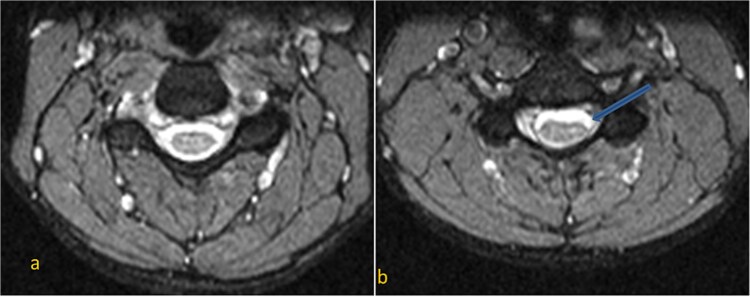

平山病(Hirayama disease, HD)是一种罕见的颈椎脊髓病,累及下颈肌瘤,引起不对称或单侧上肢远端肌肉萎缩。诊断依赖于临床表现、神经传导研究和颈椎中性位和屈曲位的MRI。我们提出一个17岁的男性无痛,进行性无力和萎缩的左前臂和手的肌肉,并伴有多汗症。最初的颈椎MRI显示颈椎前凸消失,下颈半索萎缩,前角细胞T2信号强度增加。屈曲MRI显示后硬脑膜前移,颈髓受压,静脉丛充血,后硬膜外间隙扩大并增强,证实平山病。在常规MRI检查中出现颈髓萎缩和不对称扁平的青少年男性,应怀疑为平山病。屈曲MRI对识别硬脑膜前移位及相关改变至关重要,确保准确诊断。

Hirayama disease (HD) is a rare cervical myelopathy involving lower cervical myotomes, causing asymmetric or unilateral distal upper extremity muscle atrophy. Diagnosis relies on clinical findings, nerve conduction studies, and cervical spine MRI in neutral and flexion positions. We present a 17-year-old male with painless, progressive weakness and atrophy of the left forearm and hand muscles, along with hyperhidrosis. Initial cervical spine MRI revealed loss of cervical lordosis, lower cervical hemicord atrophy, and increased T2 signal intensity in the anterior horn cells. Flexion MRI demonstrated anterior shifting of the posterior dura, cervical cord compression, venous plexus congestion, and posterior epidural space widening with enhancement, confirming Hirayama disease. In adolescent males with cervical cord atrophy and asymmetric flattening on routine MRI, Hirayama disease should be suspected. Flexion MRI is crucial for identifying anterior dural shifting and related changes, ensuring accurate diagnosis.